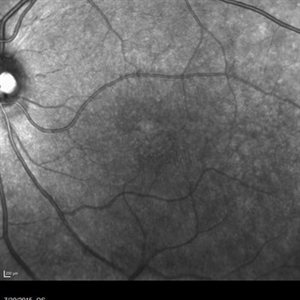

Retinal Dystrophy of 24-Year-Old Male/ AF OD

Nov 25 2015 by Zach Dupureur

Fluorescein angiography of a 24-year-old male. Juvenile retinoschisis on OCT. FA shows outer retinal staining. Could be associated with Goldman Farve Syndrome.

Photographer: Zach Dupureur OCT-C

Imaging device: Heidelberg Spectralis

Condition/keywords: Goldmann-Favre Syndrome, juvenile retinoschisis, retinal dystrophy